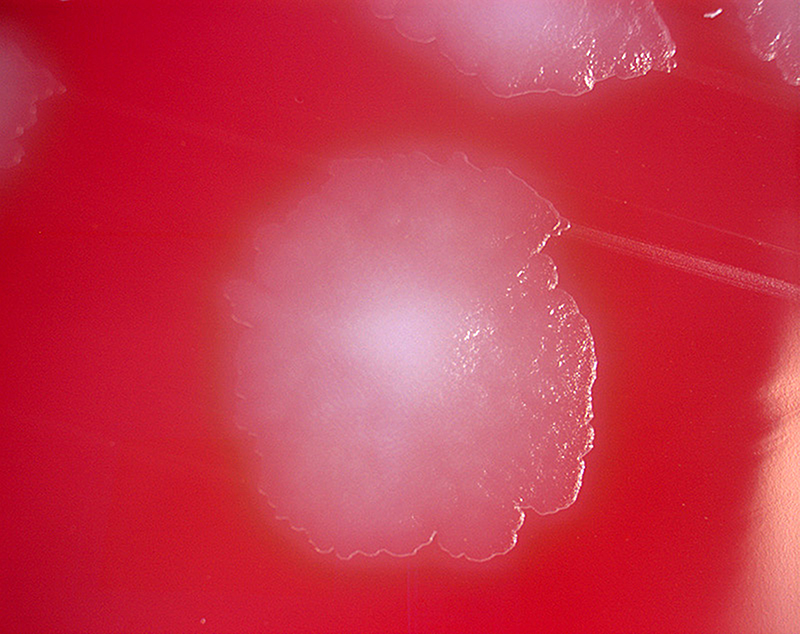

Botulism is a rare and potentially fatal illness caused by a toxin produced by the bacterium Clostridium botulinum and sometimes Clostridium butyricum and Clostridium baratii.

The bacteria that make botulinum toxin are common both in soil and water. They produce the botulinum toxin when exposed to low oxygen levels and certain temperatures.

These bacteria make spores, which act like protective coatings. Spores help the bacteria survive in the environment, even in extreme conditions. The spores usually do not cause people to become sick, even when they are eaten. But under certain conditions, these spores can grow and make one of the most lethal toxins known.

MMIZ, ErasmusMC, Rotterdam_Loes van Damme

Wikipedia

Wikimedia.org